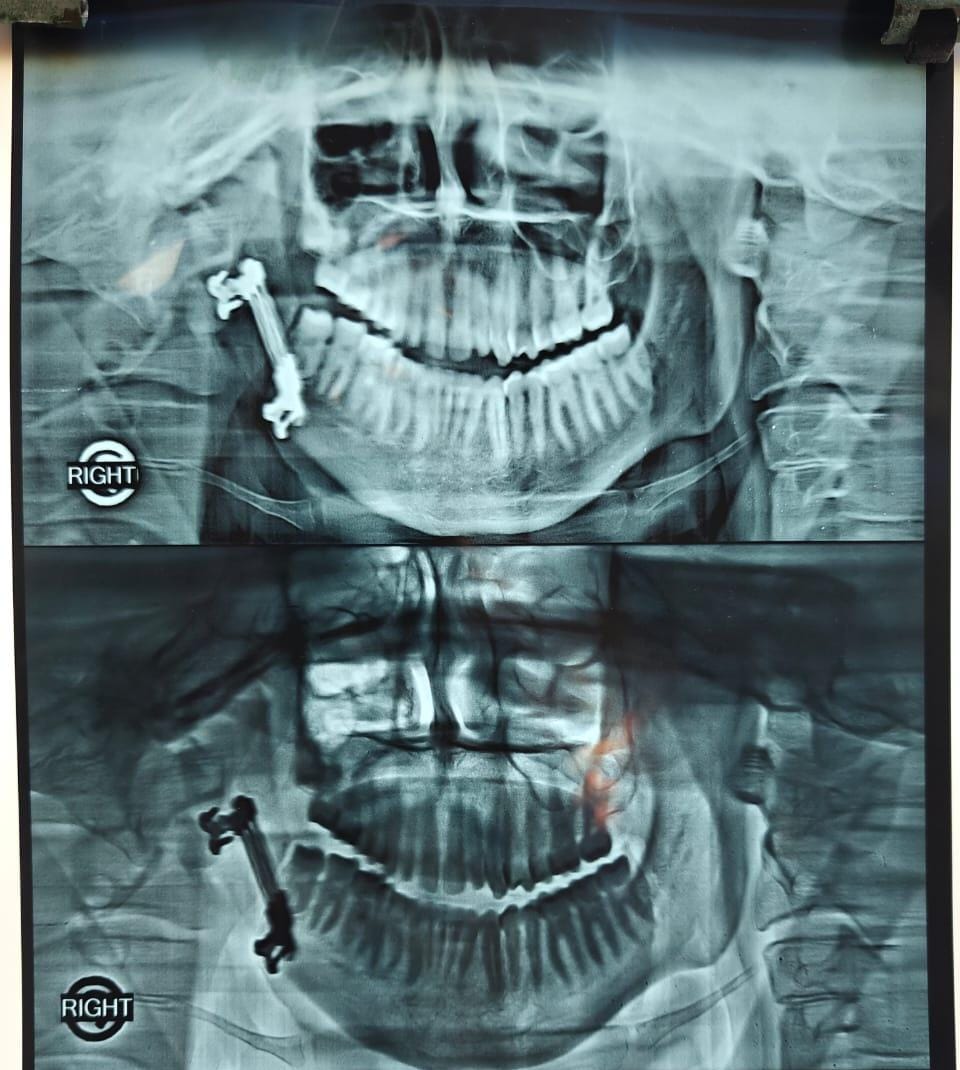

Jaw Lengthening Surgery

About Jaw Lengthening Surgery

Jaw lengthening surgery, also known as mandibular or maxillary advancement, is a procedure used to correct a short or underdeveloped jaw. This condition can affect facial appearance, bite alignment, speech, and breathing.

Dr. Saurabh Gupta performs advanced jaw lengthening procedures using modern surgical techniques to gradually extend the jaw bone, improving facial balance and functional outcomes. The treatment is carefully customized to achieve natural-looking and long-lasting results.